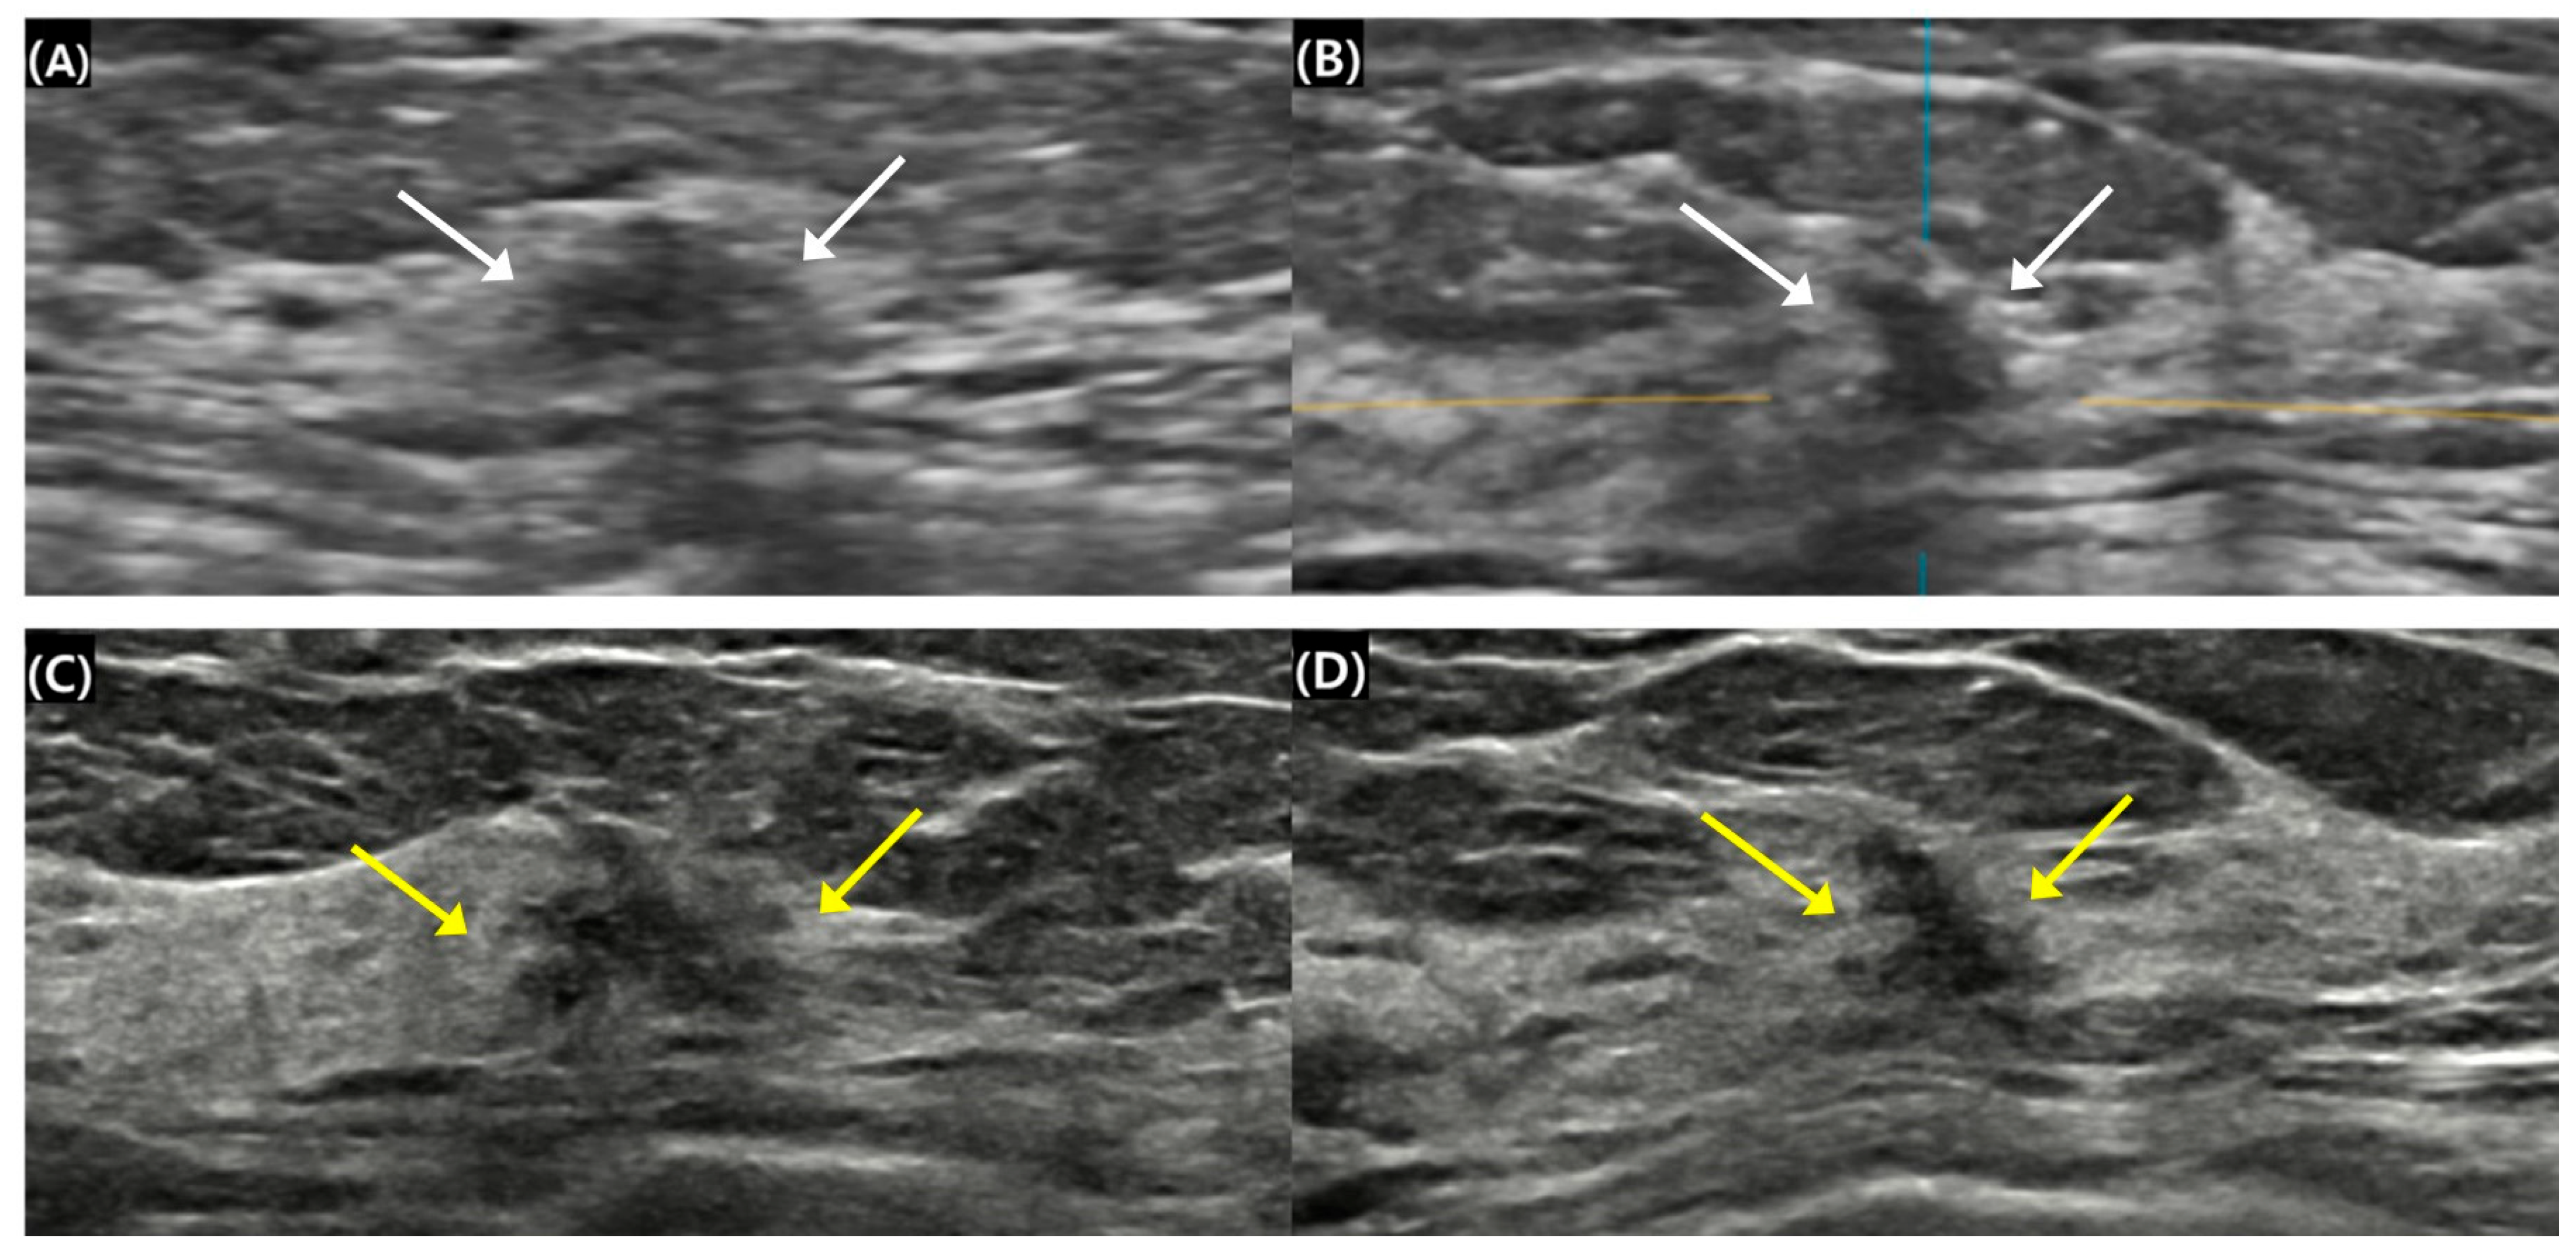

Figure 2.

Surgical histopathology revealed a 1.1 cm invasive ductal carcinoma in the left breast of a 52-year-old woman. (A,B) A 1.0 cm irregular isoechoic mass was categorized as breast imaging reporting and data system (BI-RADS) 4B on automated breast ultrasound (ABUS) (white arrows). The blue and yellow lines served as crossing directional lines to indicate the position and direction of the lesion in (B). (C,D) The mass was measured at 1.1 cm and showed more heterogeneous echogenicity. The assessment was upgraded to BI-RADS 4C on handheld breast ultrasound (HHUS) (yellow arrows). The lesion received a lower category rating on ABUS compared to HHUS. Size measurements of small breast masses were similar across both ABUS and HHUS modalities. The maximal diameters were 0.92 ± 0.30 cm for ABUS and 0.93 ± 0.29 cm for HHUS (mean ± standard deviation). No significant difference was observed between the two modalities in assessing the size of small breast masses (p > 0.05). Pathological results revealed a mean cancer size of 1.10 ± 0.42 cm. Tumor size assessments across ABUS, HHUS, and pathological reports were also comparable, with respective sizes of 0.92 ± 0.30 cm, 0.93 ± 0.29 cm, and 1.10 ± 0.42 cm, showing no significant differences (p > 0.05).

The only statistically significant difference between ABUS and HHUS was found in the final BI-RADS assessment categories based on US findings (Table 3). Cross-tabulation of the re-assigned BI-RADS categories revealed that 54.9% (28/51) of the masses had identical classifications between ABUS and HHUS. However, ABUS assigned a lower BI-RADS category than HHUS in 37.3% (19/51) of cases (p = 0.005), while still maintaining a level of suspicion for malignancy by classifying these masses as BI-RADS 4A or higher (Figure 2). No masses were categorized as BI-RADS 3 or lower on ABUS, indicating that these lesions were considered likely benign even by ABUS. In contrast, four cases (7.8%) were classified with a higher BI-RADS category on ABUS than on HHUS.